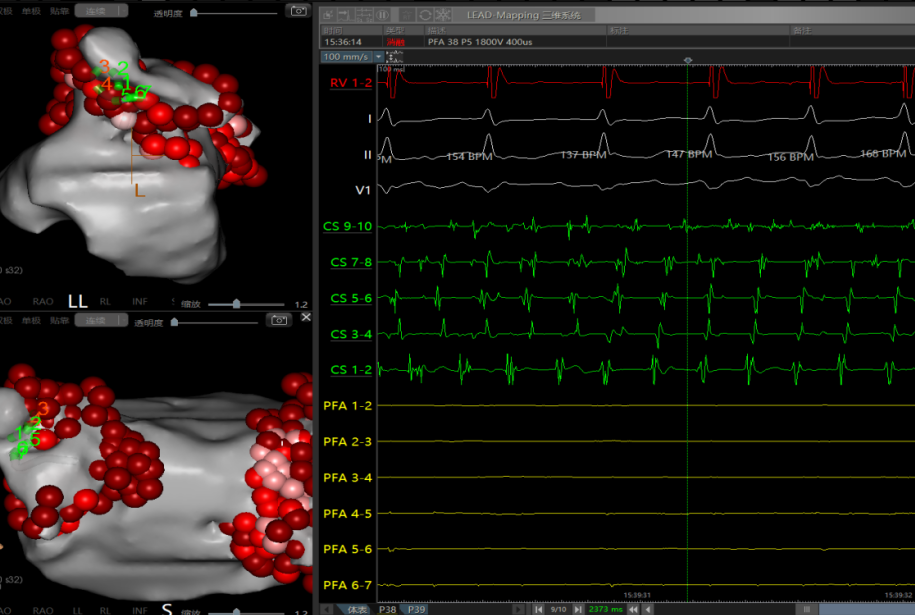

前壁消融:使用点状脉冲消融导管沿着瘢痕区域拉前壁线,最终将房扑打停,转为窦律。

顶部线消融

转为窦性心律。

术后体表&腔内心电图